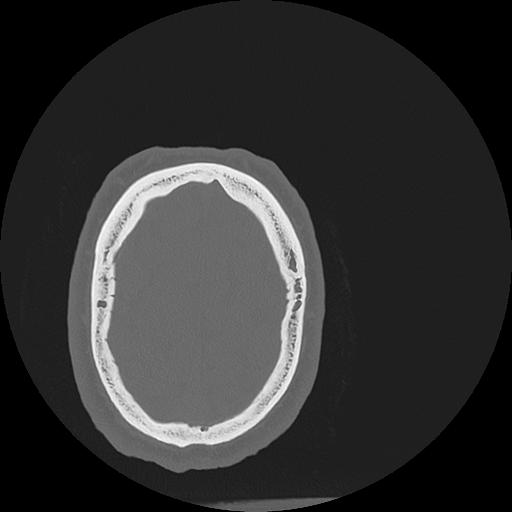

7 HUESO,,Vol,0.5,HUESO,,